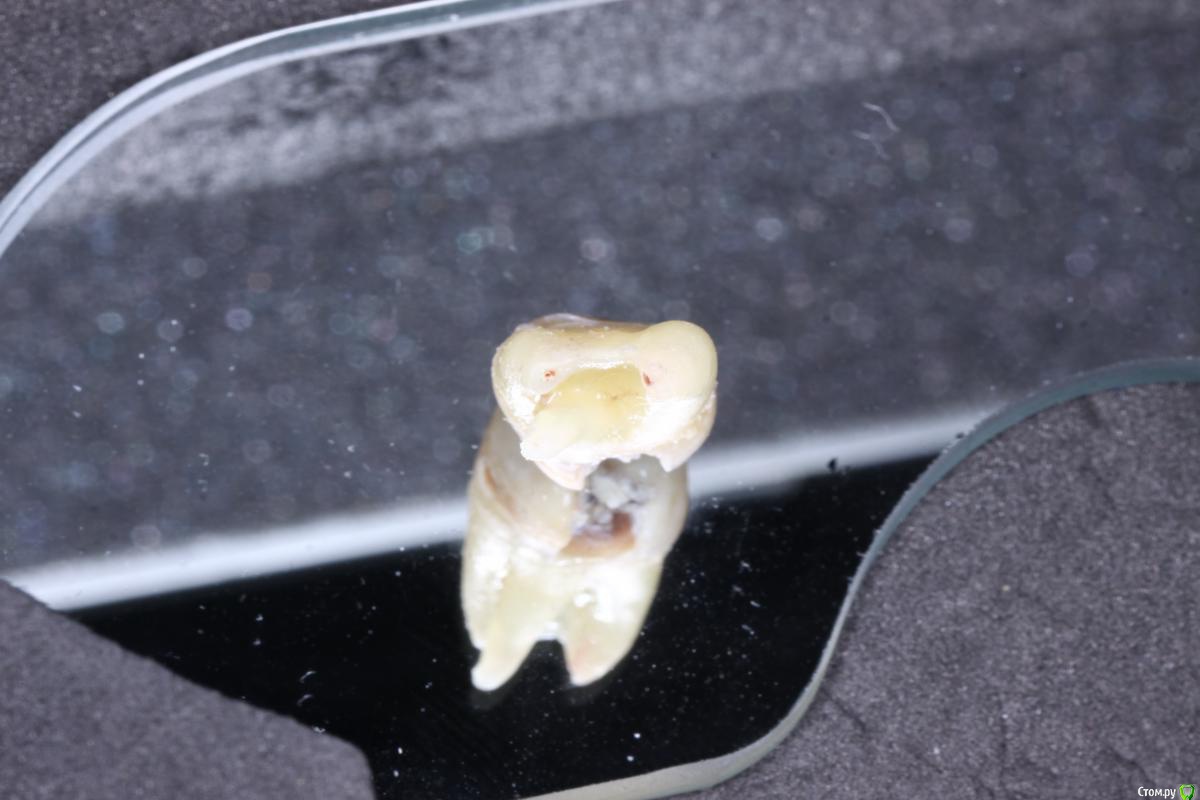

shishok Опубликовано 20 июля, 2016 Поделиться Опубликовано 20 июля, 2016 Восьмерка не особо выдающаяся,но сработал принцип-"не верь глазам своим":по Рг 3 корня,а в результате-табуретка. 5 Ссылка на комментарий